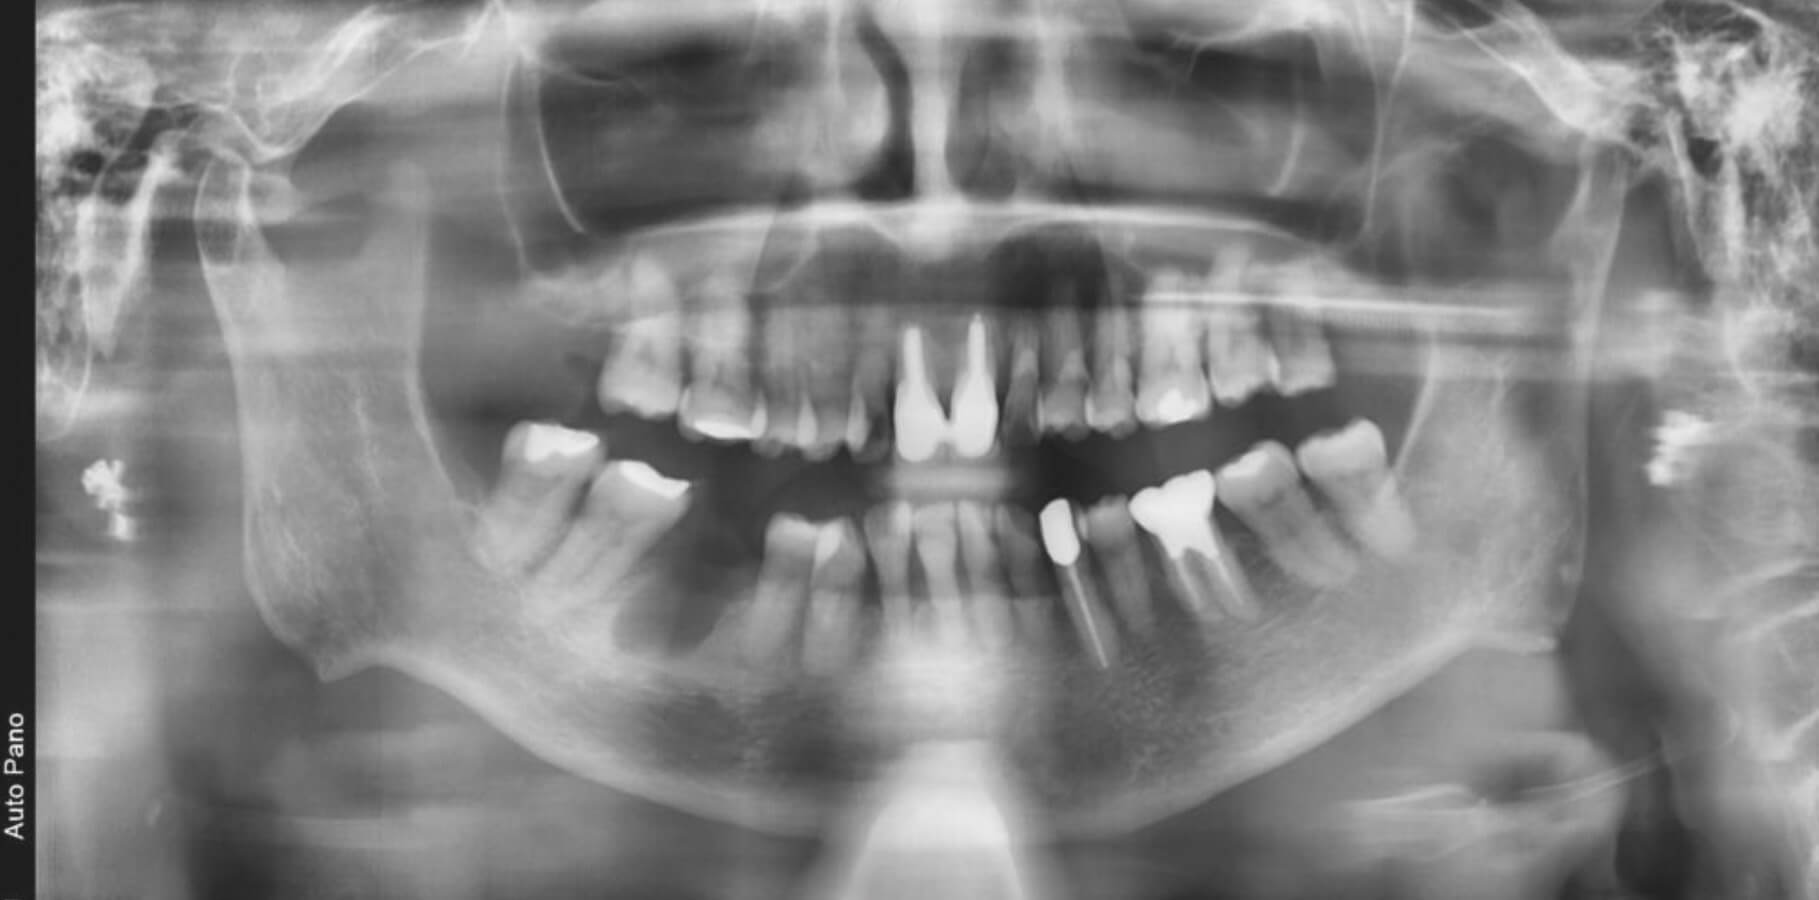

骨が足りない 骨増生を行ったインプラント症例

| 主訴 | 右下の歯を抜いて、骨が足りないのでインプラントは難しいと言われた。 ブリッジと入れ歯はしたくない。 |

| 治療内容 | 人工骨を用いて、骨増生を行い、インプラント埋入を行った。 世界シェアNo.1のストローマン社製インプラント、BLXを用いて、初期固定を得た。 また、初期固定を増加させる目的でデンサーバーの使用を行った。 担当医 里 裕太郎 |